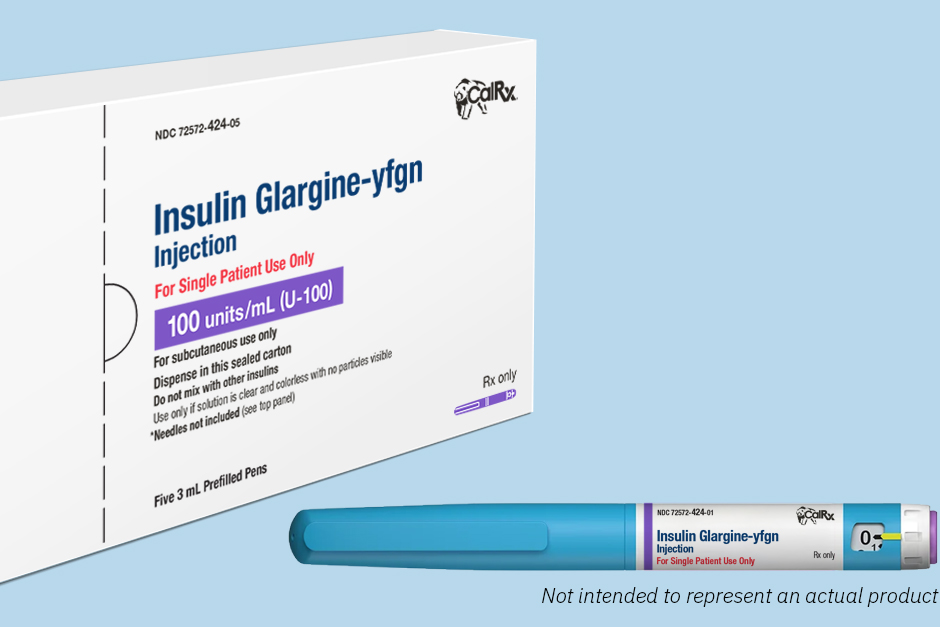

Yosemite National Park's Badger Pass Ski Area Open For Season Initiative Makes Cheaper-Cost Insulin Pens Available

Initiative Makes Cheaper-Cost Insulin Pens Available PG&E Official Recaps Widespread Tuolumne County Outage